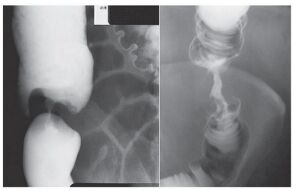

22.患者接受大腸鋇劑灌腸(barium enema)攝影的結果如下圖,最可能是下列何種疾病?(A)腸套疊 (B)惡性腫瘤 (C)腸扭轉 (D)腸炎